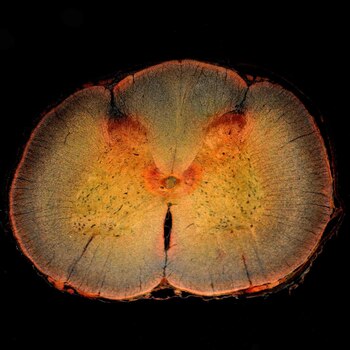

Un equipo de investigadores de la Universidad de Ingeniería de Toronto (Canadá) y la Universidad de Michigan (Estados Unidos) ha rediseñado y mejorado una enzima natural que se muestra prometedora en la promoción de la regeneración del tejido nervioso después de una lesión en la médula espinal.

Su nueva versión, detallada en la revista científica 'Science Advances', es más estable que la proteína que se produce de forma natural, y podría conducir a nuevos tratamientos para revertir el daño nervioso causado por una lesión traumática o un accidente cerebrovascular.

"Uno de los mayores desafíos para la curación después de este tipo de lesión nerviosa es la formación de una cicatriz glial", detalla la líder del estudio, Molly Shoichet. Una cicatriz glial está formada por células y bioquímicos que se unen fuertemente alrededor del nervio dañado. A corto plazo, este entorno protector protege a las células nerviosas de una lesión mayor, pero a largo plazo puede inhibir la reparación del nervio.

Hace unas dos décadas, los científicos descubrieron que una enzima natural conocida como condroitinasa ABC, producida por una bacteria llamada 'Proteus vulgaris', puede degradar selectivamente algunas de las biomoléculas que componen la cicatriz glial.

Al cambiar el entorno alrededor del nervio dañado, se ha demostrado que la condroitinasa ABC promueve el recrecimiento de las células nerviosas. En modelos animales, puede incluso llevar a recuperar alguna función perdida. Pero el progreso se ha visto limitado por el hecho de que la condroitinasa ABC no es muy estable en los lugares donde los investigadores quieren utilizarla.